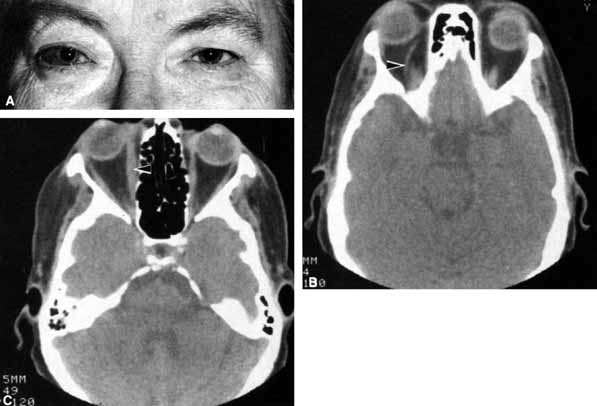

CASE 1 A 70-year-old woman presented with a 6-month history of progressive diplopia and ptosis. She demonstrated complete right third, fourth, and sixth cranial nerve palsies, and hypesthesia of cranial nerve V1 (Fig. 22A). The right pupil was dilated. Computed tomography (CT) disclosed an intracavernous aneurysm (see Fig. 22B). The so-called superior orbital fissure syndrome occurs when an infiltrative, inflammatory, or ischemic event occurs within the superior orbital fissure, but not in the orbital apex.4 A complete superior orbital fissure syndrome occurs when all the neurovascular components passing through the superior orbital fissure are damaged, producing a total ophthalmoplegia, ptosis, and anesthesia of cranial nerve V1 (see Fig. 22A). The pupil may be dilated, miotic, or midposition and fixed, depending on the balance of parasympathetic and sympathetic damage. The superior ophthalmic vein, best seen on CT, may be dilated if venous outflow from the orbit is obstructed. Clues to venous outflow obstruction are increased intraocular pressure, fullness of the upper eyelid, and hyperemia of the deep Tenon's vessels. Ophthalmoscopically, the retinal veins may be dilated. The effect of a lesion in the superior orbital fissure or the anterior cavernous sinus cannot be differentiated clinically (see Fig. 22B). When the posterior cavernous sinus becomes involved, hypesthesia of cranial nerve V2 may also be present. The only difference between a superior orbital fissure syndrome and an orbital apex syndrome is the presence of visual loss caused by optic nerve involvement. Visual acuity, color vision, or the visual field are abnormal. An ipsilateral relative afferent pupil defect is present. CASE 2 A 30-year-old man noted diplopia and right ptosis for the past month. The patient demonstrated normal vision and symmetric pupils but had a neurogenic ptosis (Fig. 23A) and limited right supraduction (Fig. 23B). Otherwise his extraocular movements were full. CT demonstrated an intracranial aneurysm of the posterior communicating artery aneurysm (Fig. 23C). Anatomically, the third cranial nerve branches into its superior and inferior divisions as it enters the orbit through the superior orbital fissure. Superior branch damage results in ptosis (levator muscle) and decreased supraduction (superior rectus muscle). Inferior branch damage results in decreased adduction (medial rectus), decreased infraduction (inferior rectus), decreased excycloduction (inferior oblique), and a dilated pupil (parasympathetic). Anatomically, a cranial nerve III branch nerve lesion seems to imply an anterior cavernous sinus or orbital apex localization. However, functionally, the third cranial nerve may bifurcate in the intracranial portion of the nerve, so cranial nerve III branch nerve palsies have been demonstrated with intracranial lesions. The localizing finding of a cranial nerve III branch nerve lesion is therefore not absolute (see Fig. 23).46 CASE 3 A 12-year-old child was referred by his school nurse because he had been complaining intermittently of double vision and the nurse had noted intermittent right ptosis. The child presented with a right ptosis and limited infraduction of the left eye (Fig. 24A). The ptosis worsened with prolonged up-gaze. A Cogan lid twitch was noted on the right with upward saccades. Injection of 1 mg of edrophonium resulted in complete resolution of diplopia and ptosis (Fig. 24B). The diagnosis was myasthenia gravis. Most orbital and cavernous sinus lesions produce afferent and efferent palsies in an anatomic pattern, for example, the superior orbital fissure has cranial nerves III, IV, VI and V1. When the pareses are not localized anatomically, or when there is variability in findings over time, one should include carcinomatosis or myasthenia gravis (see Fig. 24) in the differential diagnosis. Fatigability and a Cogan lid twitch strongly suggest myasthenia gravis. CASE 4 A 52-year-old woman presented with diplopia when looking to her right. She had noted a red right eye for the past 3 months (Fig. 25A). Visual acuity was 20/20 in both eyes and the pupils were normal. The right eye was limited in abduction. Forced duction testing showed abduction of the right eye to be restricted. Intraocular pressures were 23 mm Hg OD, and 15 mm HG OS. CT showed a dilated right superior ophthalmic vein (Fig. 25B) which was shown to be caused by a dural cavernous fistula. The right medial rectus muscle was also enlarged (Fig. 25C) because of blood engorgement, reducing muscle compliance, which accounted for the restricted abduction. Carotid cavernous fistulas can develop either as a result of trauma or spontaneously.47 A direct carotid cavernous fistula results from a tear in the intracavernous carotid artery with arteriolization of the cavernous sinus and superior orbital vein. Concomitant cranial nerve III, IV, VI, V1 and V2 paresis, elevated intraocular pressure, proptosis, and distention of the deep Tenon's vessels anteriorly (see Fig. 25A) with neuroradiologic evidence of an enlarged superior ophthalmic vein are common (see Fig. 25B). Ophthalmoplegia may also occur on a restrictive basis because of engorgement of the extraocular muscles with blood (see Fig. 25C).36 Dural carotid cavernous fistulas occur where small branches of the intracavernous carotid rupture, allowing access of arterial blood to the cavernous sinus. Typically, the findings are similar to a direct carotid cavernous fistula but of less magnitude. There is no history of trauma, and typically occurs in older persons. However, there is crossover between these two types of carotid cavernous fistula. An excessive ocular pulse tonographically may be helpful in the diagnosis of a carotid cavernous fistula in such cases.48 CASE 5 A 51-year-old woman was referred by her internist for left proptosis. The patient had noted diplopia for the past month but denied blurred vision or pain. Past history was significant for breast carcinoma requiring mastectomy. Vision was 20/20 in both eyes and the pupils were normal. Extraocular movements of the right eye were limited. Forced ductions were restricted. Exophthalmometry readings were 14 mm OD and 18 mm OS (Fig. 26A). CT disclosed a mass encircling the right globe (Fig. 26B). Biopsy disclosed metastatic scirrhous breast carcinoma retracting the right globe.